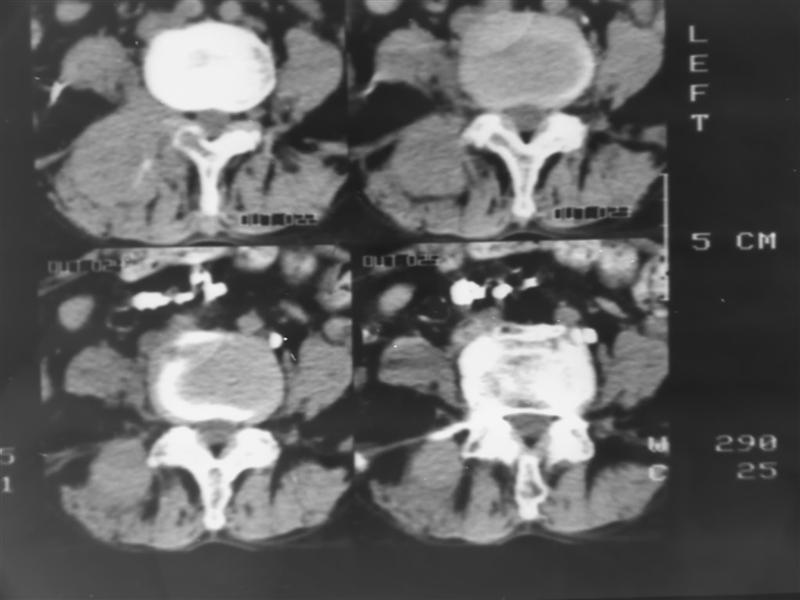

以下是引用老爱克斯新网客在2007-9-27 17:59:00的发言:[br]多个椎体及椎弓跟骨质破坏,并见软组织肿块,符合转移瘤改变,

以下是引用wqs571018在2007-9-27 16:48:00的发言:[br]支持:多发病变,骨质破坏伴软组织块影,符合转移.